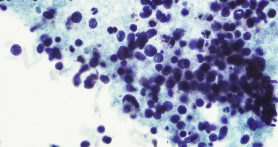

Most patients with lung cancer have non-small cell lung cancer. However, around 15% of patients have a less-common type called small cell lung cancer. Small cell lung cancer progresses more rapidly than non-small cell, so it’s often detected at later stages.

Describing small cell lung cancer